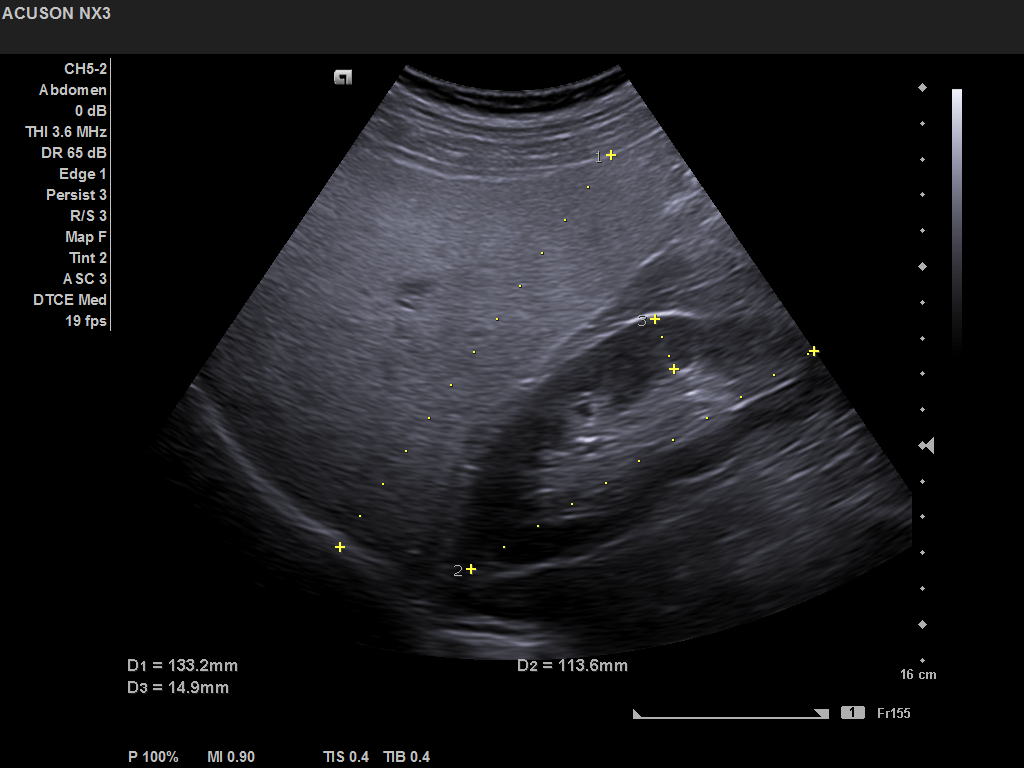

Ultrasound findings in Actinomyces infection of the neck [Aug/Sep 2020]September 25, 2020Student Image Challenge 69October 16, 2020 Student Image Challenge 68 Student Image Challenge #68 1 / 1 Student Image Challenge #68 This pathology is the most common liver disease in Western countries. What is this aspect suggestive of? Hepatic metastases Cholangiocarcinoma Diffuse hepatic steatosis Cirrhosis Focal nodular hyperplasia Incorrect ....Please see the correct answer highlighted Correct: Diffuse hepatic steatosis Hepatic steatosis is suggested by the increased echogenicity and beam attenuation, resulting in renal cortex appearing relatively hypoechoic compared to the liver parenchyma. Your score isThe average score is 100% LinkedIn Facebook VKontakte 0% Restart quiz Case courtesy of Prof Adrian Săftoiu EFSUMBAdmin Related postsStudent Image Challenge 112Read more Comments are closed.